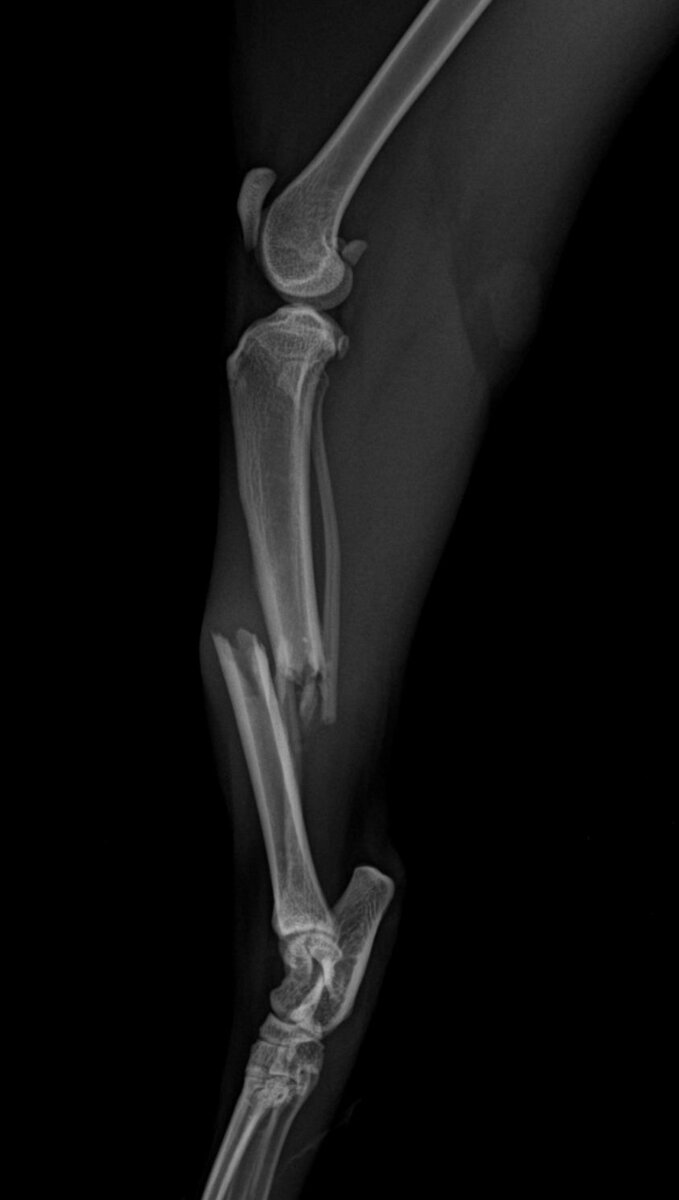

А спустя время увидели, что Маша едва передвигается, волоча за собой заднюю лапку.

Рентген показал, что это перелом. Нужна пластина в месте перелома. С пластиной, понятное дело, выпуск на улицу невозможен.